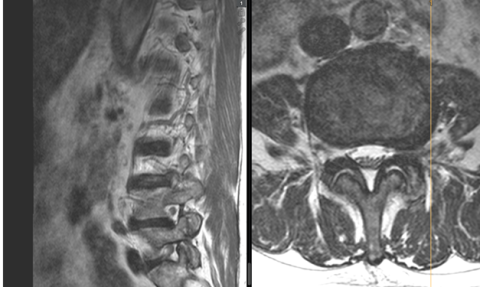

Cases of (extreme) lateral disc herniation that lead to compression of the exiting nerve root are not common and often very painful (Figure 1). Studies solely focused on such cases of disc herniation are rare and, as a result, mostly only present low case numbers. As a large Spine Centre, we have the opportunity to collate and analyse sufficient amounts of case data, even on this rare condition.

From an anatomical point of view, the different segments of the spine differ from one another. Specifically, the L5/S1 segment, the junction between the lumbar spine and the sacral bone, is unique and can pose a particular challenge. To complicate matters, accessibility for the surgeon at the L5/S1 level is impeded by the pelvis. Lateral disc herniation is often connected to degenerative changes to segments. Hence, scoliotic changes (lateral curvature of the spine), for example, may intensify the pressure on the nerves.